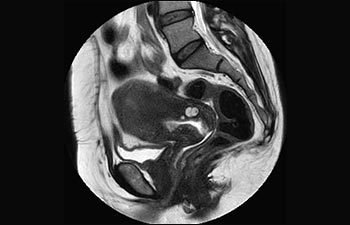

Sehen Sie selbst, was die ersten Nutzer von Ingenia Prodiva 1.5T über ihre Erfahrungen mit dem System und dessen Auswirkung auf ihre radiologische Praxis berichten.